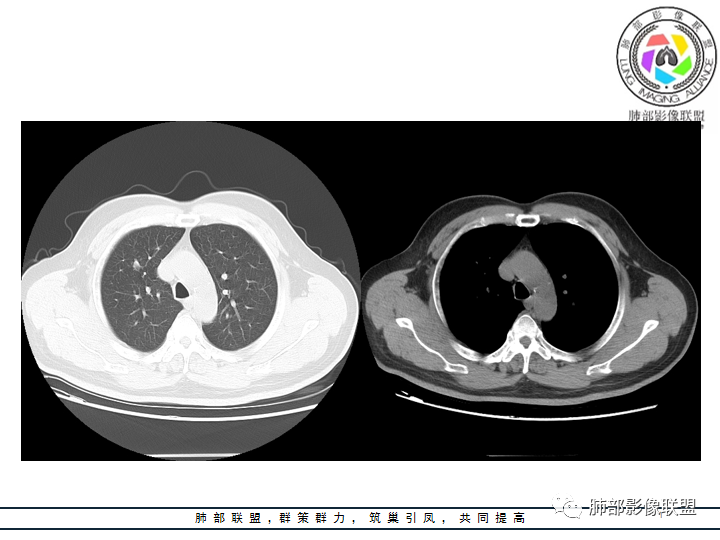

老年男性患者,长期吸烟史,没有呼吸系统临床表现。胸部CT示右肺上叶实性密度结节影,密度均匀,未见空洞及钙化,边缘较光整,未见分叶及毛刺。血管影旁现侧出,支气管进入并截断,不均匀强化。

赵国千:男性62岁,右肺上叶前段见结节,可见支气管穿行其中,增强轻度强化,倾向良性肿瘤,首先错构瘤、腺瘤;恶性肿瘤,淋巴瘤、淋巴上皮瘤样癌,这个比较难。

郑昊宇:老年男性 右肺结节 ,考虑肿瘤性病变,影像关键是判断是否有支气管进入,需要薄层和重建,如果进入,明显强化,考虑类癌可能,如果没进入,考虑psp。

冯连彩:老年男性,有吸烟史,因腹疼入院查体发现肺部结节,右肺上叶前段结节,边缘光滑,浅分叶?支气管进入后截断,血管贴边,密度较高,有强化,考虑PSP或炎性假瘤?鉴别淋巴瘤,类癌?